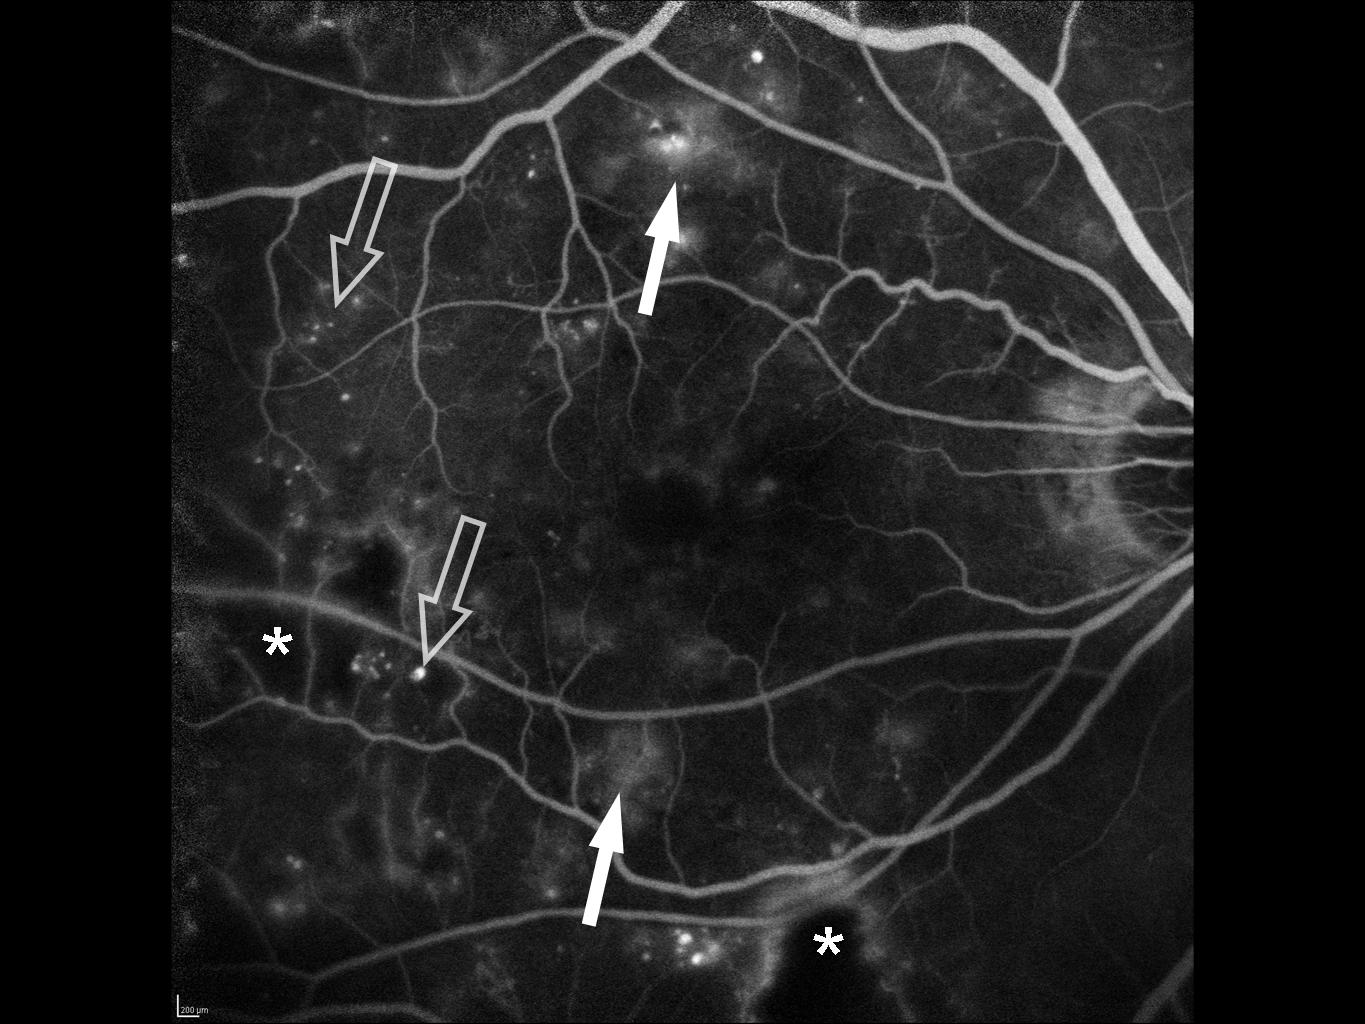

1. Рис.1 | |

2. Рис.2 | |

3. Рис.3 | |

4. Рис.4 | |

5. Рис.5 | |

6. Рис.6 | |